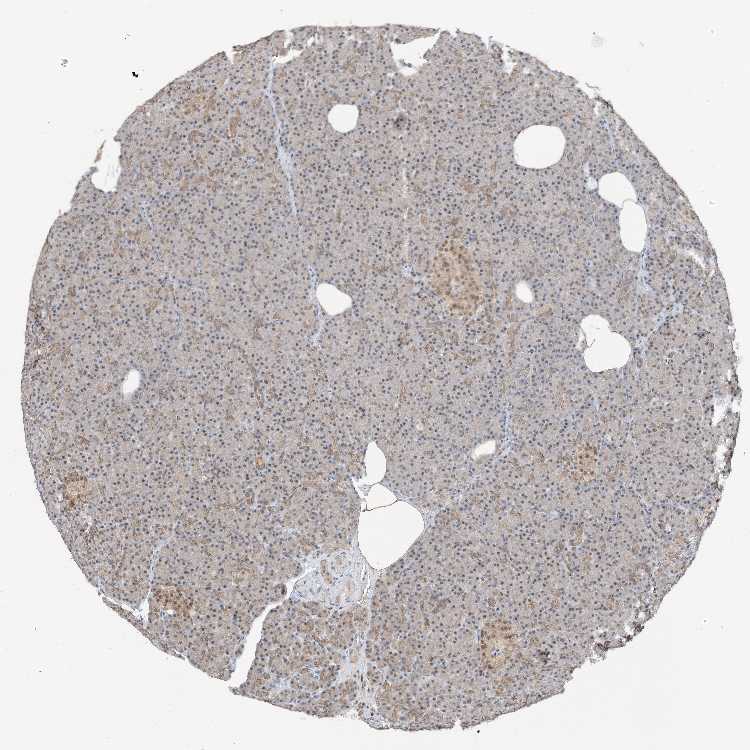

PANCREAS - Antibody stainingi

Antibody staining in the annotated cell types in the current human tissue is reported as not detected, low, medium, or high, based on conventional immunohistochemistry profiling in selected tissues. This score is based on the combination of the staining intensity and fraction of stained cells.

Each image is clickable and will lead to virtual microscopy that enables deeper exploration of all samples and also displays staining intensity scores, fraction scores and subcellular localization as well as patient and tissue information for each sample.

Antibody HPA023924Antibody HPA031526

Exocrine glandular cells HighMedium

Pancreatic endocrine cells MediumMedium